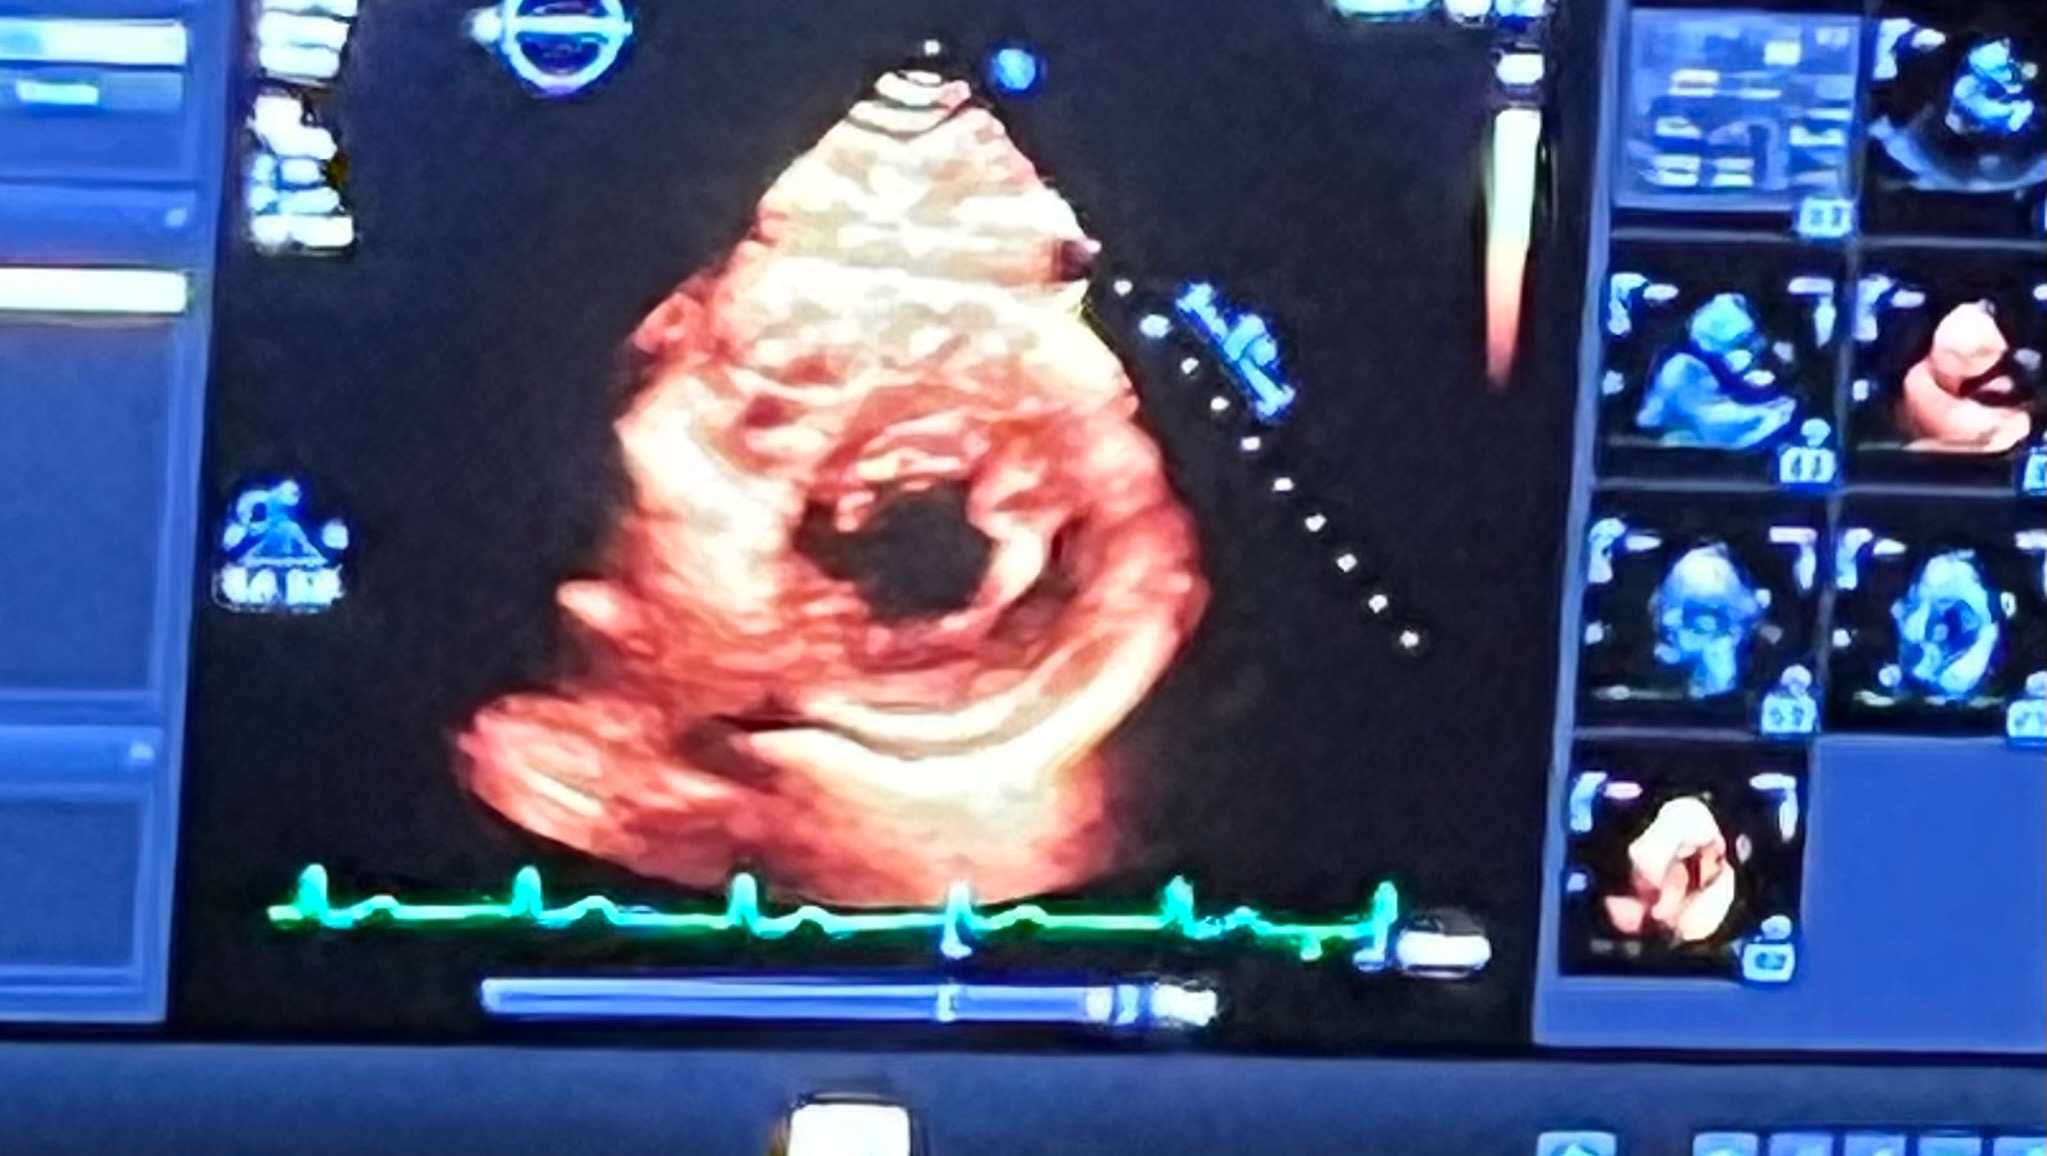

At 35 years old, I've been diagnosed with Hypertrophic Obstructive Cardiomyopathy (HOCM), a grave heart condition that has completely disrupted my life. It not only affects me, but also places a significant weight on my devoted partner.

HOCM has stripped me of the simplest of joys & has made even the most effortless tasks completely impossible, with the constant fear of sudden complications always on my mind. This diagnosis has completely turned my life upside down. I have had to resign from work & go on disability, heavily plan out many routine tasks in my day-to-day life, if I can manage to get out of bed that day. This includes normal activities such as going to the store or just folding laundry. This condition has completely taken away my ability to maintain the active and independent lifestyle that I once had.

Since my diagnosis in January, my life has been a terrible sequence of hospital admissions, heart failure scares, and an exhausting regimen of medications, including a newly FDA-approved treatment (CAMZYOS) that requires constant monitoring to prevent devastating consequences.

I want to thank everyone for their efforts, donations, & kindness thus far. I have been on specialty heart medication, made it to all of my weekly appointments at the heart failure clinic, echocardiogram screenings, & cardiac rehab. I also made a trip to the Mayo Clinic in Scottsdale, Arizona for more tests & a plan of action. I wouldn’t have been able to get this far without everyone’s support, so thank you again!

That being said, the current situation is as follows... The testing and appointments at the Mayo Clinic in Scottsdale were more detailed & informative of my hearts condition(s) we’re dealing with. Unfortunately, it is worse than anticipated. Luckily, I don’t have any scar tissue at this time, but I do have three obstructions, one being a birth defect & the other two are caused by my genetic disease (muscle thickness blocking the pathway for sufficient amounts of blood to pass through my heart). This is deemed a complex case, in which only 3 surgeons in the United States are equipped to handle (2 at Mayo Clinic in Rochester, Minnesota & 1 at Cleveland Clinic, Ohio).